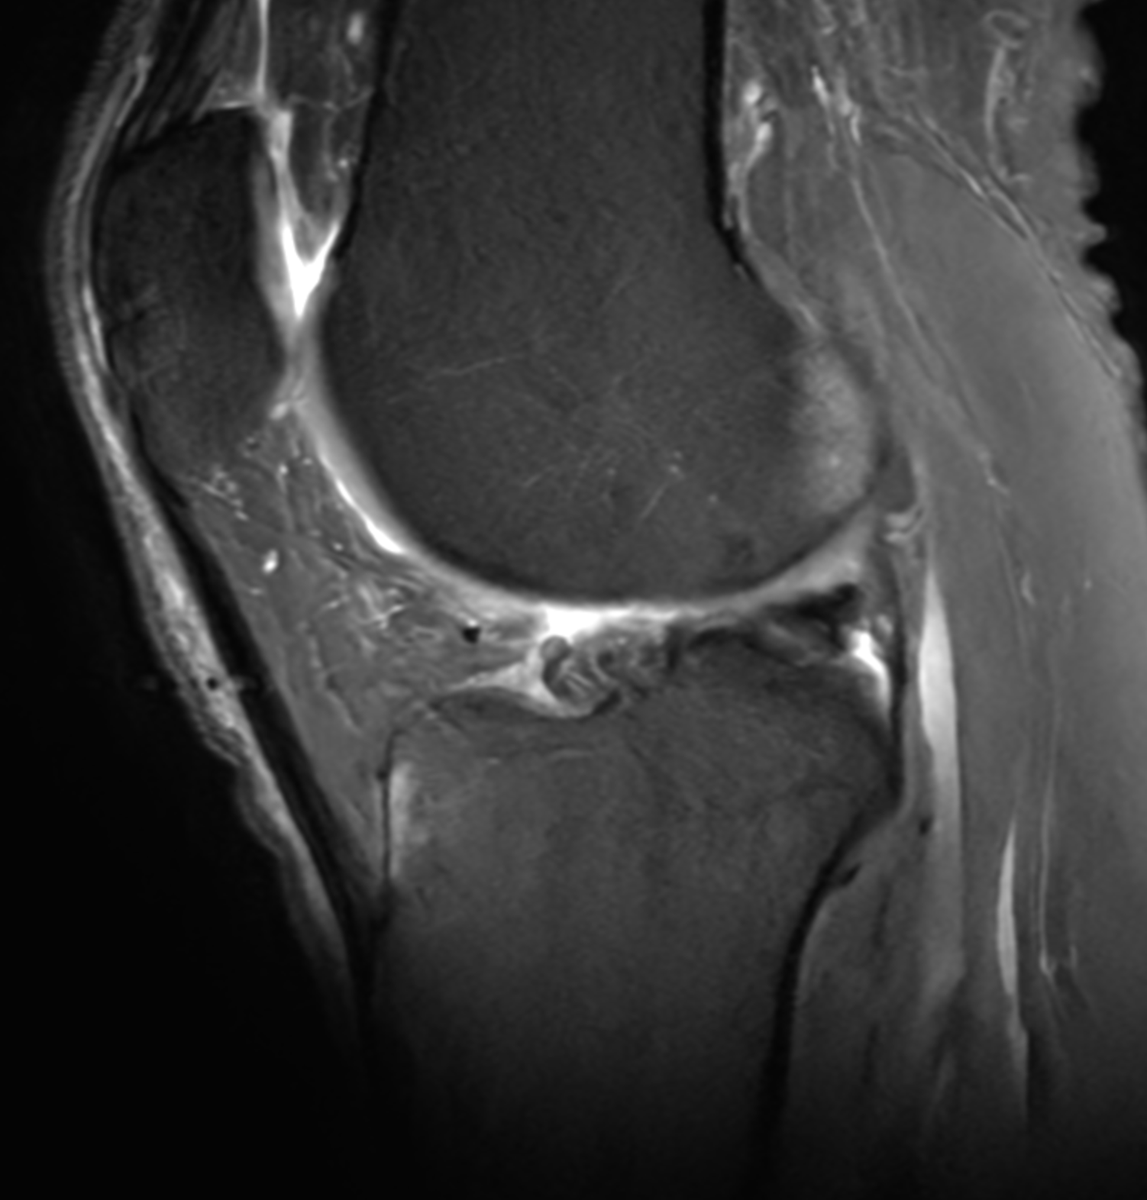

60 yo runner. Also lifts 3x/week. Stable lateral meniscus tear and a small cartilage defect for 10 years. New pain.. worse. Mostly anterior, anterolateral. Pain with loading, jumping, etc... but on landing, not the jump. in other words... axial load hurts.

New MRI: mostly anterior BME deep to PT insertion.

Stress reaction from the tendon or load??